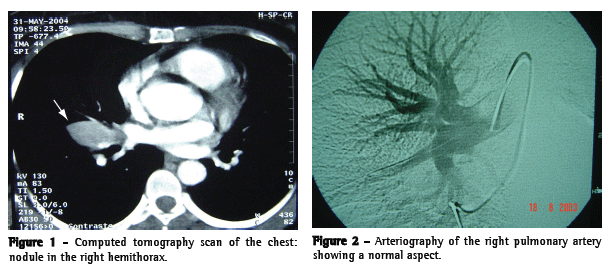

A computed tomography scan revealed a nodule of approximately 3 cm in diameter. The nodule was quite near the pulmonary artery, and vascular origin therefore could not be ruled out (Figure 1).

We performed pulmonary arteriography, which did not reveal a relationship between the nodule and the pulmonary artery (Figure 2). The bronchoscopy findings were normal. The thoracotomy was performed, and an extrapulmonary nodule was found between the superior and middle lobes. The nodule was easily resected.